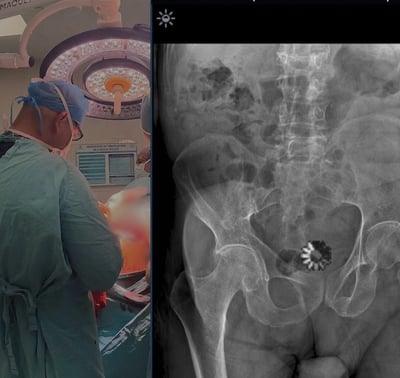

Galería Médica

Traumatólogos y Ortopedistas en Toluca Disponibles las 24 Horas.